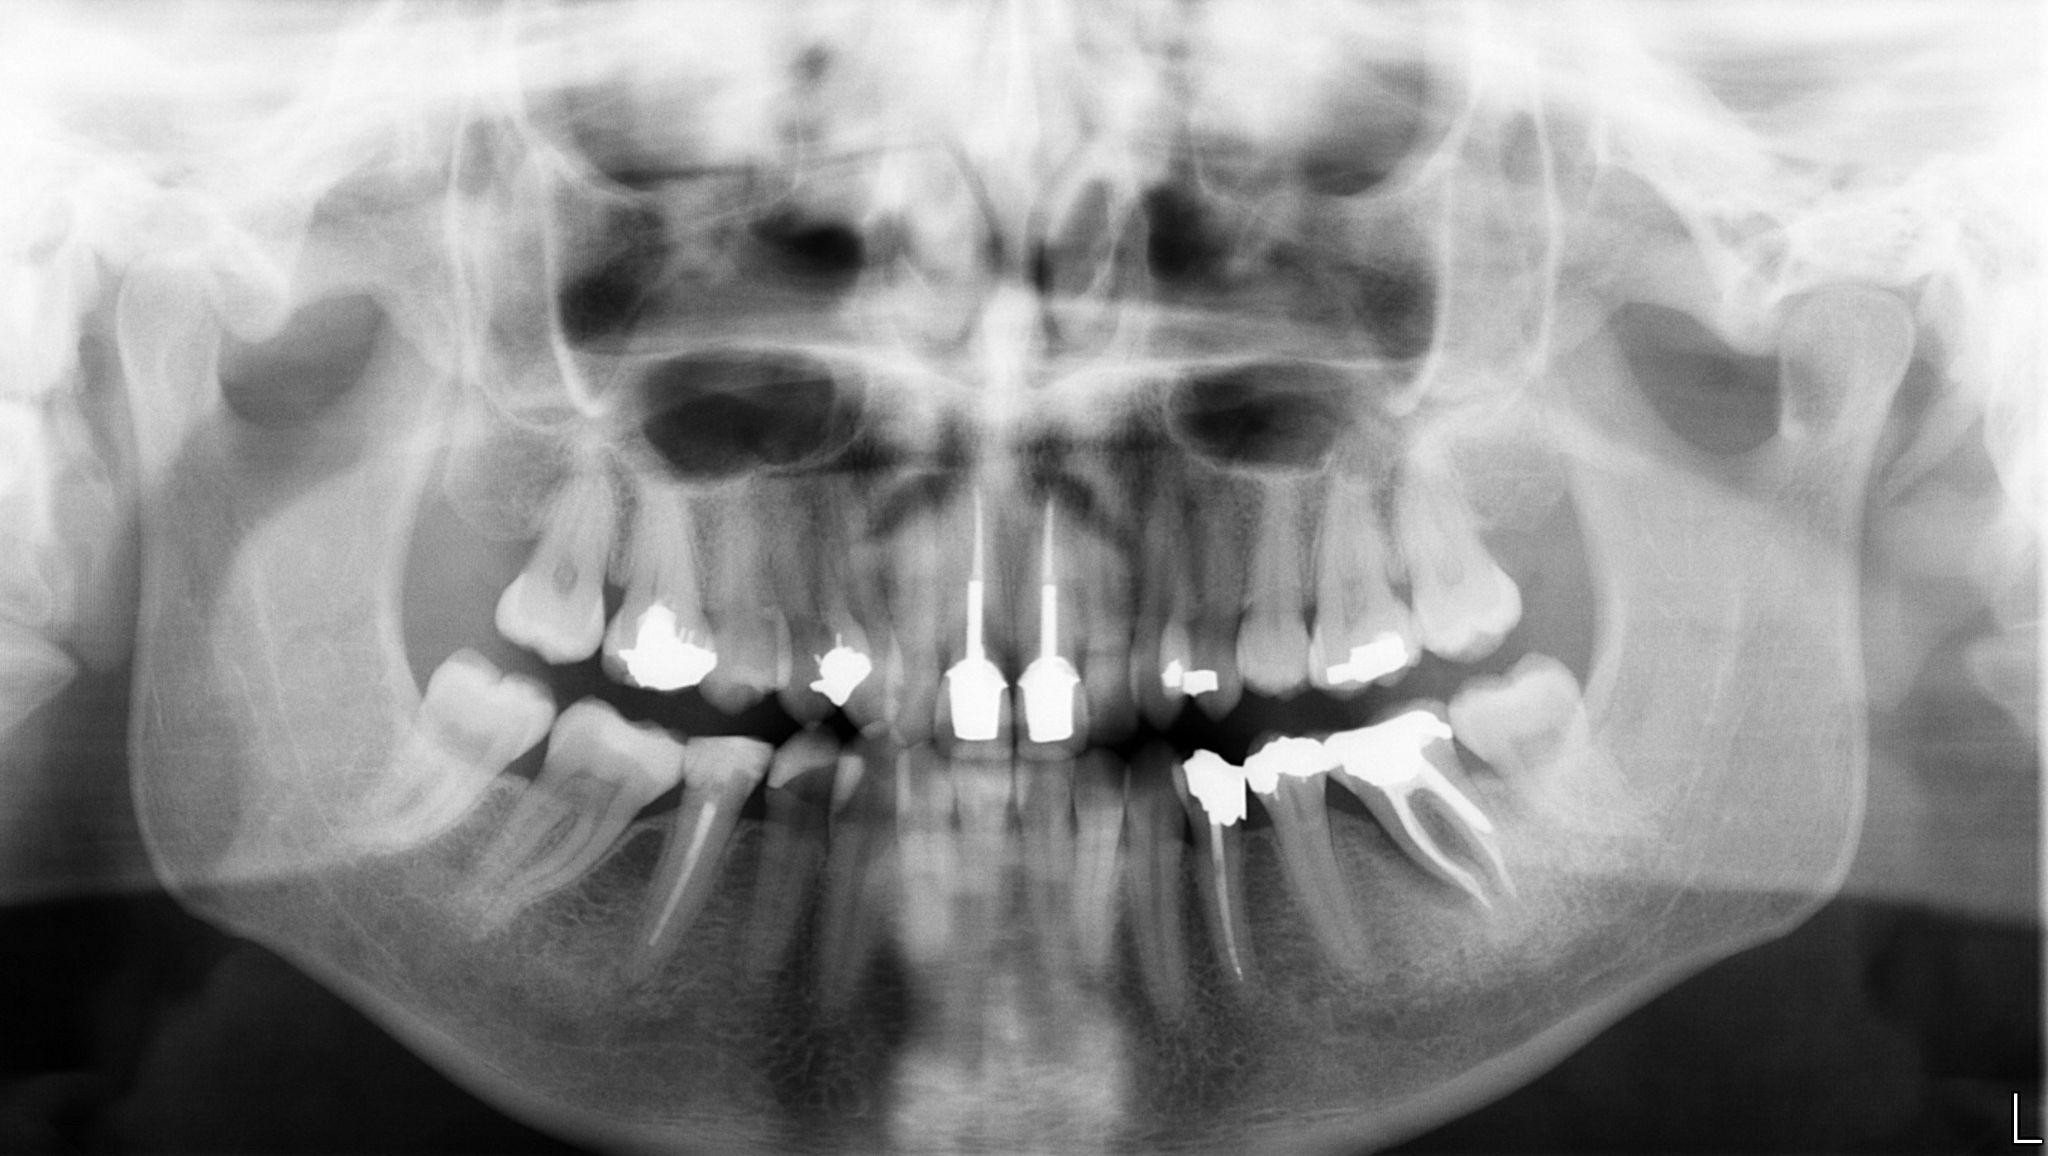

16 / 25

16. What option cannot be selected for the upper jaw of this panoramic X ray?

17 / 25

17. What option cannot be selected for the lower jaw of this panoramic X ray?

18 / 25

18. What option cannot be selected for the upper jaw of this panoramic X ray?

19 / 25

19. What option cannot be selected for the lower jaw of this panoramic X ray?

20 / 25

20. What option can be selected for the upper jaw of this panoramic X ray?

21 / 25

21. What option cannot be selected for the lower jaw of this panoramic X ray?

22 / 25

22. What option cannot be selected for the upper jaw of this panoramic X ray?

23 / 25

23. What option cannot be selected for the lower jaw of this panoramic X ray?

24 / 25

24. What option cannot be selected for the upper jaw of this panoramic X ray?

25 / 25

25. What option cannot be selected for the lower jaw of this panoramic X ray?